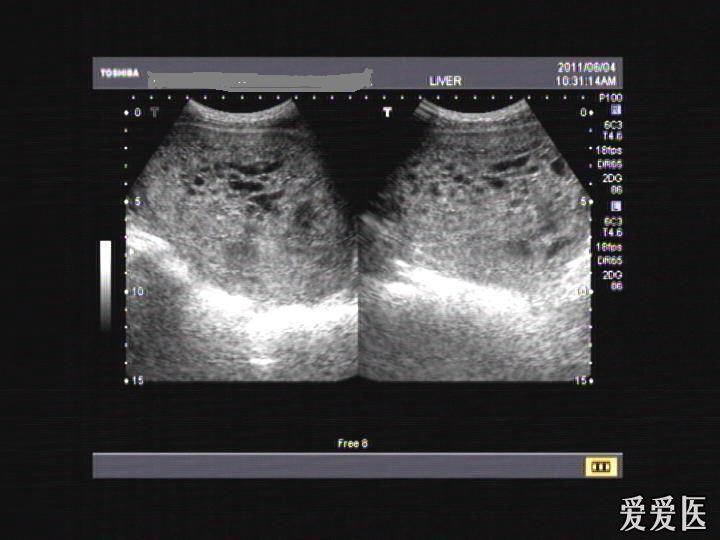

专家门诊1例——双胎合并葡萄胎

图片尺寸1024x768